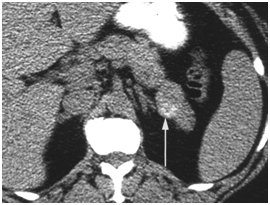

CT scan has many advantages since it can be easily performed, is non-invasive and the images are easily interpretable for the surgeon. Insulinoma typically appear as well-defined, rounded, homogeneously masses of the pancreas. Because the majority of insulinoma are usually smaller than 2cm, dynamic CT scan should be performed; the sensitivity of the dynamic CT scan in the detection of insulinoma ranges from 30% to 66%. Dual-phase contrast spiral CT scan is more sensitive than other noninvasive imaging studies. In a group of seven patients with tumors that were biochemically proven but not previously located by ultrasonography, CT scan, or magnetic resonance imaging, six of seven tumors ranging from 6 to 18 mm were detected by dual-phase spiral CT scan. Atypical CT scan imaging of insulinoma includes hypoattenuating masses on enhanced CT or intra-arterial dynamic CT, cystic masses, and calcified masses (Figure 1–3).26–30

Figure 1 Insulinoma in an 87-year-old man with intractable hypoglycemia. Dual phase CT scan through the pancreas demonstrates a subtle, well-defined 1-cm enhancing lesion (arrow) in the pancreatic neck. A small cyst is also seen. A well-differentiated 1.2-cm ICT was completely excised at surgery. Histologic stains were positive for insulin. The hypoglycemia resolved after surgery. 23